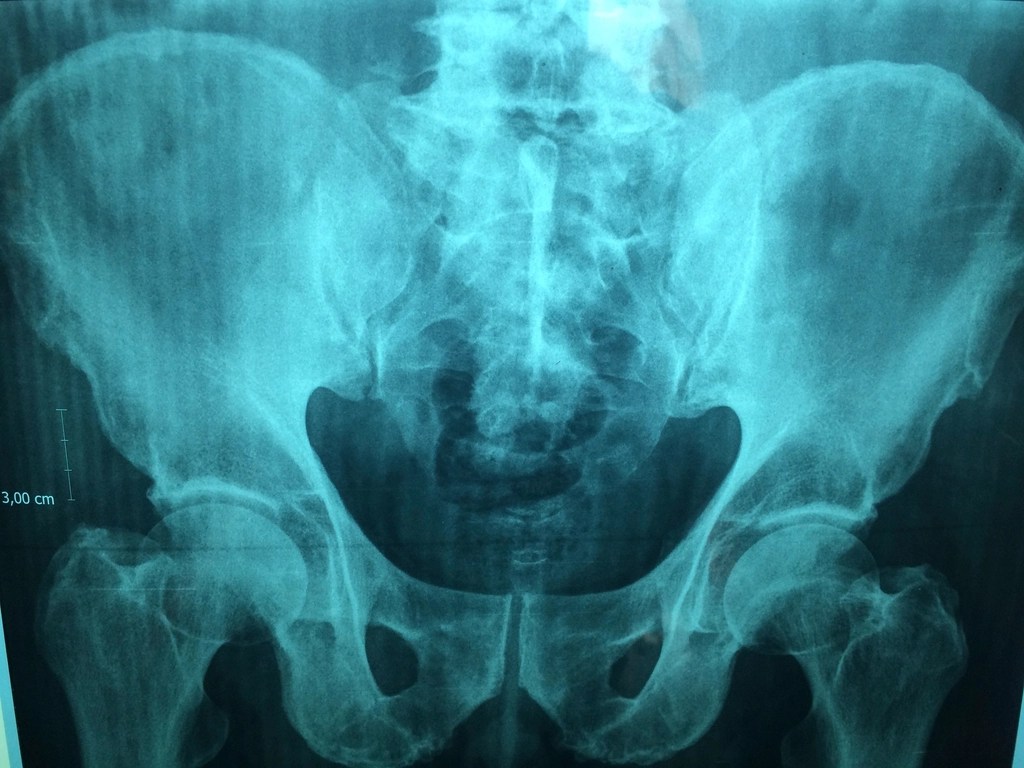

An x-ray revealed osteoarthritis in both hips.

This week MRI results revealed avascular necrosis in both femurs.